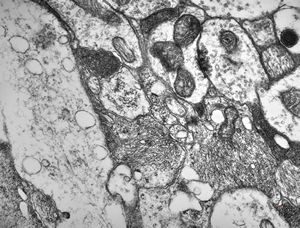

F,50y. | progressive multifocal leukoencephalopathy- viral particles in a glial cell

F,50y. | progressive multifocal leukoencephalopathy- viral particles in a glial cell

F,50y. | progressive multifocal leukoencephalopathy- viral particles in a glial cell